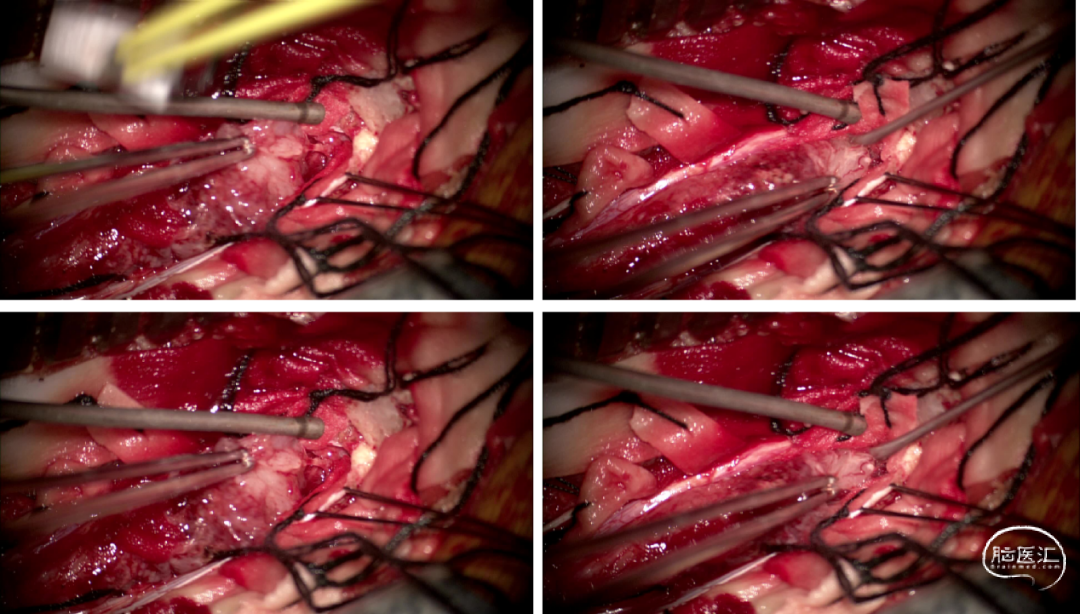

手术情况

硬脊膜张力高,脊髓向背侧膨出,与脊髓腹侧粘连紧密,肿瘤挤压脊髓,肿瘤边界分离,减少对胸髓的牵拉,降低了术后患者神经功能发生的概率,术后患者肢体麻木症状改善。